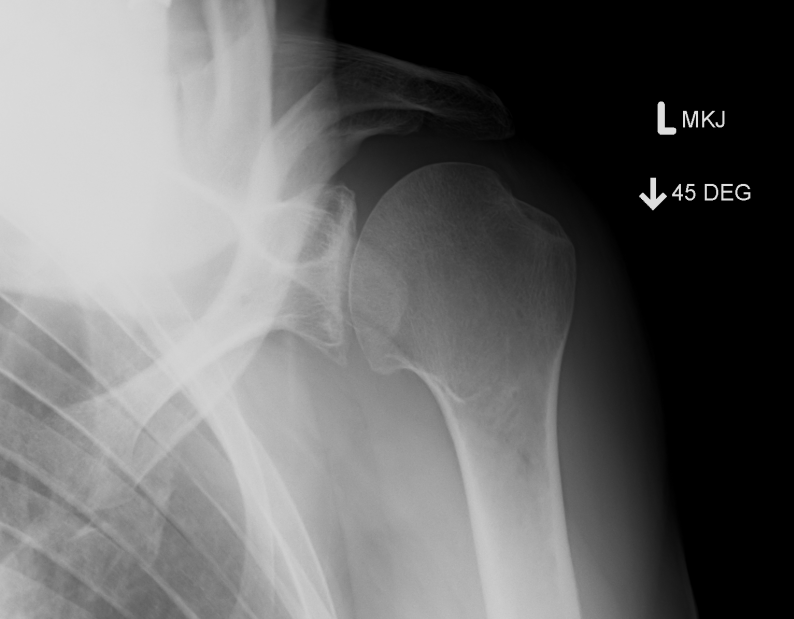

Garth View / Apical Oblique

True AP with 45o caudal tilt

- to show anterior / inferior capsule

- bony bankhart / Hill Sachs

- standing with plate behind joint

- 45° caudal tilt / 45° in coronal